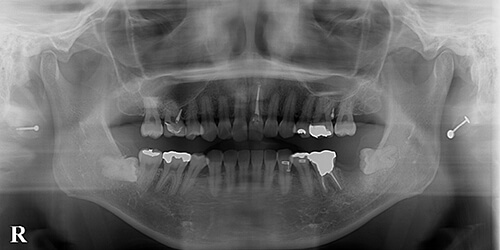

【治療中】

左下7(第2大臼歯)抜歯後です。矯正を始めるなら、完全に創傷が感知する前(7相当部に骨が出来てしまう前)に矯正を始めるのが適当かと思われます。